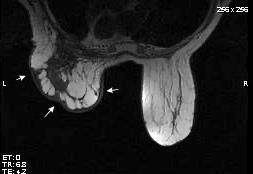

Tumor desmoide (“Fibromatosis agresiva”)

T1: Isointensos con músculos.

T2: Señal intermedia y de alta intensidad.

Presencia frecuente de áreas curvilíneas y lineales dentro de la lesión